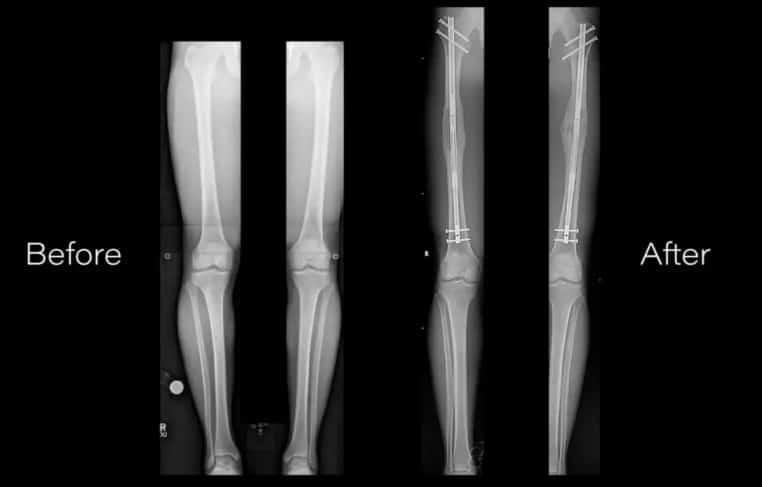

Quelle que soit la raison, les médecins peuvent désormais exaucer leur vœu. Bien sûr, il faudra mettre la main à la patte pour profiter de ce genre de chirurgie ! La Cleveland Clinic explique qu’il existe deux méthodes, selon les convenances du patient. La première consiste à utiliser un cadre métallique comme fixateur.

À l’intérieur de l’os, les médecins insèrent un support relié au cadre. La procédure implique de devoir marcher avec la tige en métal, que le patient doit visser chaque jour. Par ailleurs, le patient doit attendre un certain temps avant d’atteindre la longueur recherchée.

La deuxième opération est un peu plus compliquée. En effet, elle requiert une grande dextérité venant du médecin. La moindre erreur pourrait conduire à de graves conséquences ! Mais cette chirurgie a l’avantage d’être plus esthétique, puisqu’il n’y a aucun support ni aucune tige métallique qui dépasse.